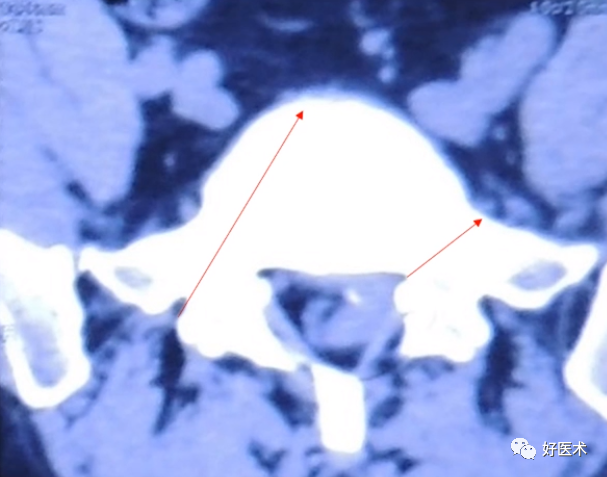

透视判断椎管

透视腰椎正位:上下终板成单边;椎弓根(猫眼)对称;棘突居中。

透视腰椎侧位:上下终板成单边;椎弓根上下缘单边;椎体后缘成单边。

实际情况:没有专业的手术透视工作人员;正位和地面垂直;侧位和患者垂直;正位看猫眼内外,侧位看椎弓根上下。

判断:透视正位,椎管外的长度设定为A;透视侧位,椎体外的长度设定为B;如果A大于或者等于B,定位针不在椎管内;如果A明显小于B,定位针在椎管内。

透视结果(优秀):①正位:定位针在猫眼内;②侧位:定位针在椎弓根正中,和椎体轴向平行;③目标椎体正确。

透视结果(及格):①正位:定位针突破猫眼内缘;②侧位:定位针在椎体内,方向和轴线不平行,预计椎弓根螺钉不会突破椎体;③目标不明确。